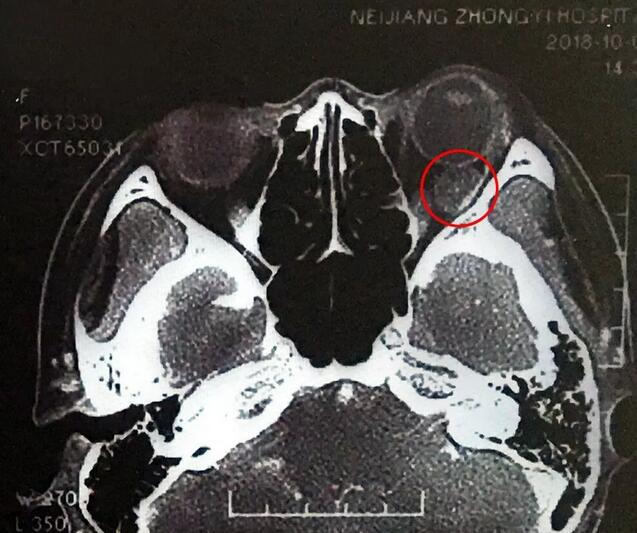

小何是四川南部县人,今年20岁,在内江上大学。今年9月底开始,出现头痛、反复呕吐,吐得连药都吃不下。医生建议小何做了脑部CT,“结果显示左眼眼球后部有个东西,经过进一步检查竟是肿瘤!”这对小何来讲真是个晴天霹雳。

在成都金沙9001以诚为本,经过详细检查,罗清礼教授根据他40余年的丰富经验,判断为淋巴血管瘤。“现在,虽然她双眼的视力都是1.0,但是眼内肿瘤已经接近眼球那么大了,若不及时手术必将失明。”

罗教授介绍,淋巴血管瘤早期症状并不明显,“一般人感冒是不会头痛、呕吐的。小何的感冒非常幸运,她感冒后引起淋巴增生,导致肿瘤内出血,然后引起了头痛、呕吐等症状,让她能够尽早发现了肿瘤。”患者的肿瘤体积较大,位置较深,位于眶间且紧挨着视神经,手术稍有差错,就可能导致患者视力丧失、大出血等情况发生。得知手术风险后,患者和家属表示非常理解并信任罗教授,坚决要求手术医治。